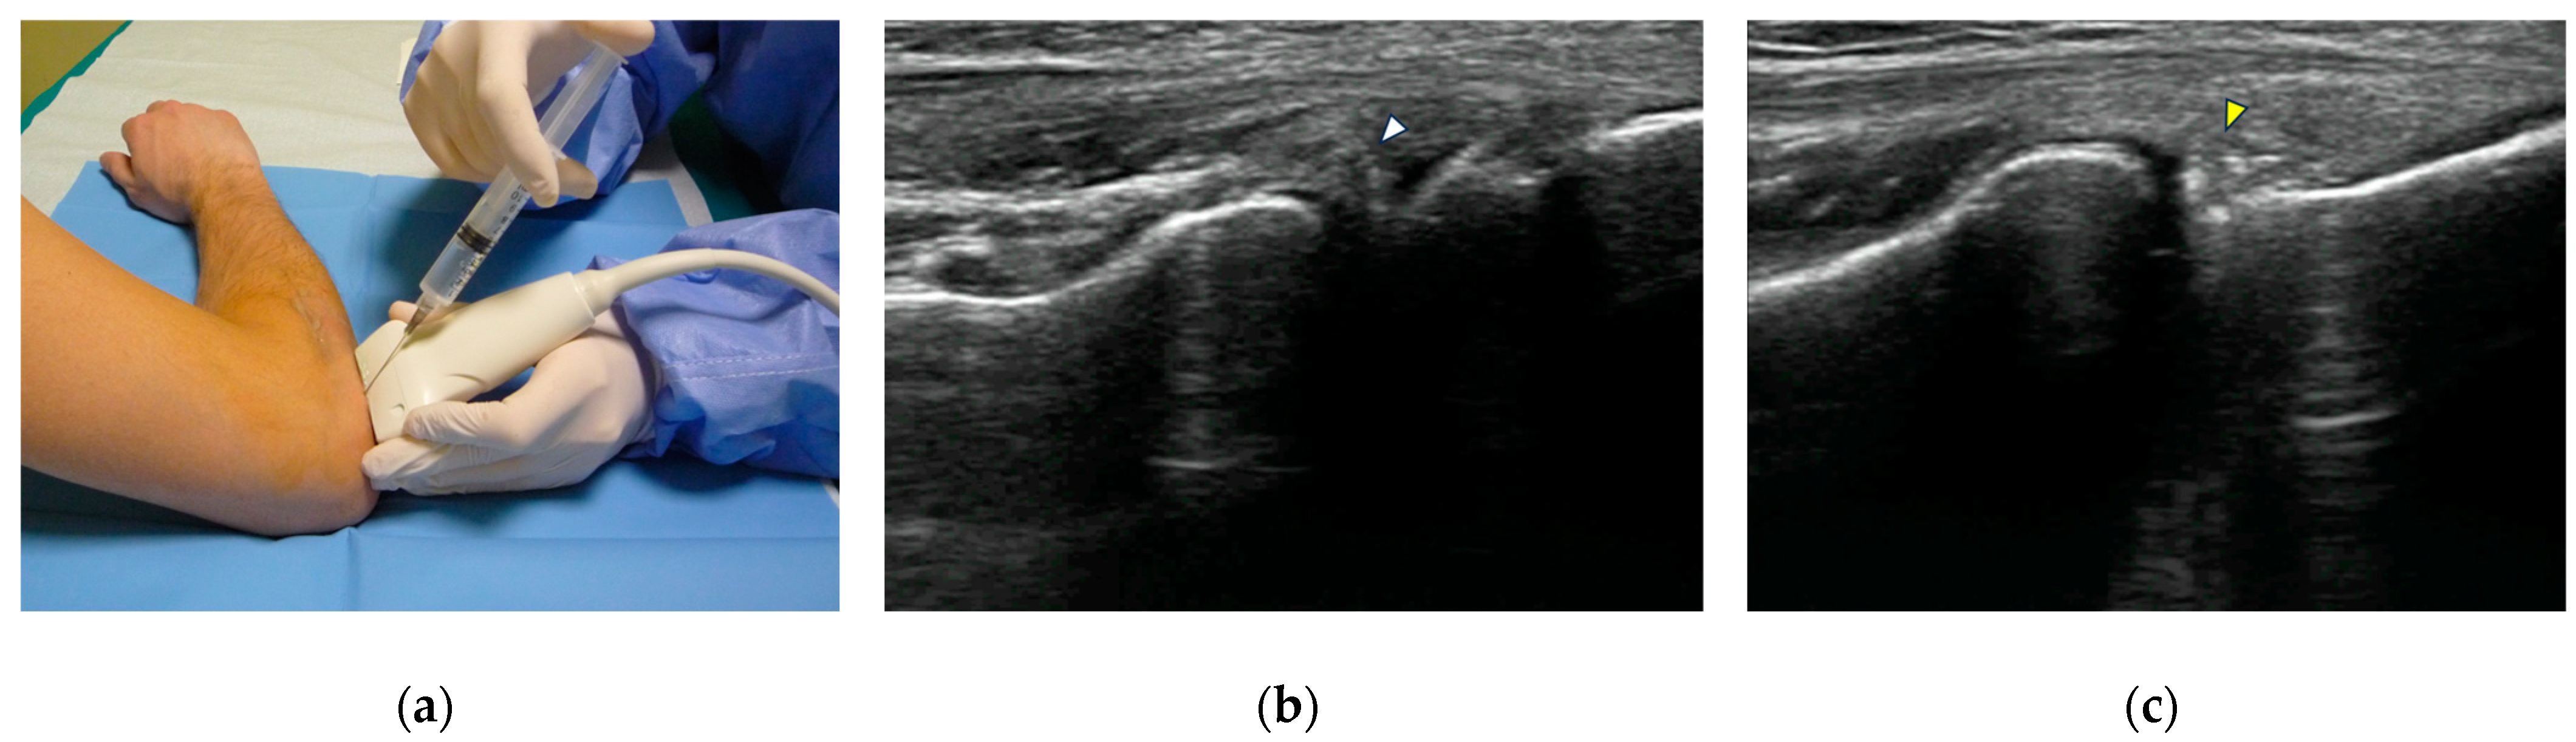

When preparing for elbow arthrography, a small, 1.5-inch (3.8 cm) 25G needle is inserted either in the radio-humeral compartment, with the patient exposing the lateral elbow by sitting down (Figure 1) or lying supine with the arm behind the back, or in the olecranon fossa with a posterior transtriceps approach [16]. The injecting needle can be positioned in an in-plane modality to allow for tracking of its trajectory from the access point to the intended target site, or in an out-of-plane modality, depending on operator preference [22]. To mitigate the discomfort associated with intra-articular puncture, a local anesthetic agent, typically 2–3 mL of lidocaine hydrochloride, may be administered. If excessive resistance is encountered during injection, and contrast fails to flow into the articular recess as anticipated, the needle should be slightly withdrawn and repositioned. As a rule of thumb, the CT arthrography examination should be performed as soon as possible after the injection to avoid compromising image quality, as intra-articular iodinated contrast will begin to disperse rather quickly: an in vivo study has shown that its half-life within the joint space can range from 30 to 60 min.

Figure 1.

US-guided intra-articular injection. (a) The injecting needle is inserted at the level of the radio-humeral joint, using an out-of-plane approach, with the transducer positioned along the long axis of the common extensor tendon; (b) US guidance allows monitoring the intra-articular placement of the needle tip (white arrowhead) and demonstrates the correct outflow of injectate; (c) as the injection is complete and the needle is withdrawn, hyperechoic intra-articular contrast medium is visualized in the radio-humeral recess (yellow arrowhead).